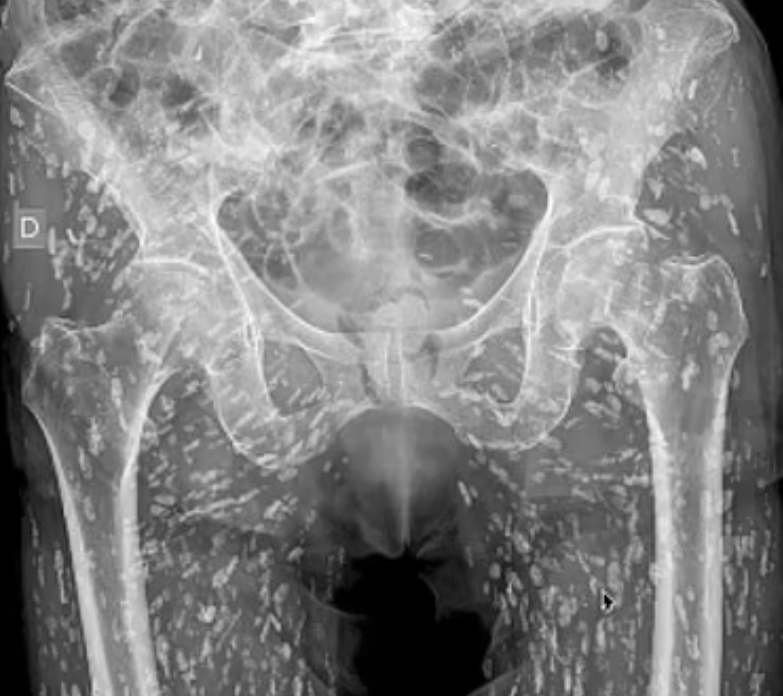

Muž zažil šok, aký si nevedel ani predstaviť. Keď mu lekári urobili röntgenové vyšetrenie, zistili, že jeho telo je doslova posiate stovkami vajíčok pásomnice. Snímka odhalila množstvo drobných útvarov pripomínajúcich zrnká ryže, ktoré sa napokon ukázali ako cysty spôsobené parazitickou infekciou.

Zarážajúci prípad zverejnil na sociálnych sieťach lekár urgentnej starostlivosti z Floridy Sam Ghali. Röntgen označil za jeden z najšialenejších, aké kedy videl. Podľa jeho slov sa pacient nakazil po konzumácii surového alebo nedostatočne tepelne upraveného bravčového mäsa, ktoré obsahovalo larvy pásomnice.

Najviac znepokojujúce na celom prípade je fakt, že muž o infekcii vôbec netušil. Do nemocnice prišiel pre bolesť bedra po páde a röntgen mal slúžiť len na vylúčenie zranenia. Namiesto toho lekári objavili rozsiahle parazitické postihnutie. V dnes už virálnom videu Dr. Ghali neskrýval šok: „Cysty sú úplne všade. Je ich nespočetne veľa, ani sa nedajú spočítať. Môžu sa dostať do ktorejkoľvek časti tela. V tomto prípade sa výrazne rozšírili do mäkkých tkanív v oblasti bokov a nôh.“

Infekcia spôsobená pásomnicou Taenia solium, známa ako taenióza, vzniká po požití vajíčok pásomnice v kontaminovanom alebo nedostatočne tepelne spracovanom mäse. Keď sa cysty usadia v tkanivách, hovorí sa o ochorení cysticerkóza, ktoré je obzvlášť nebezpečné v prípade, že zasiahne mozog alebo nervový systém. V takom prípade ide o neurocysticerkózu, ktorá môže byť život ohrozujúca.